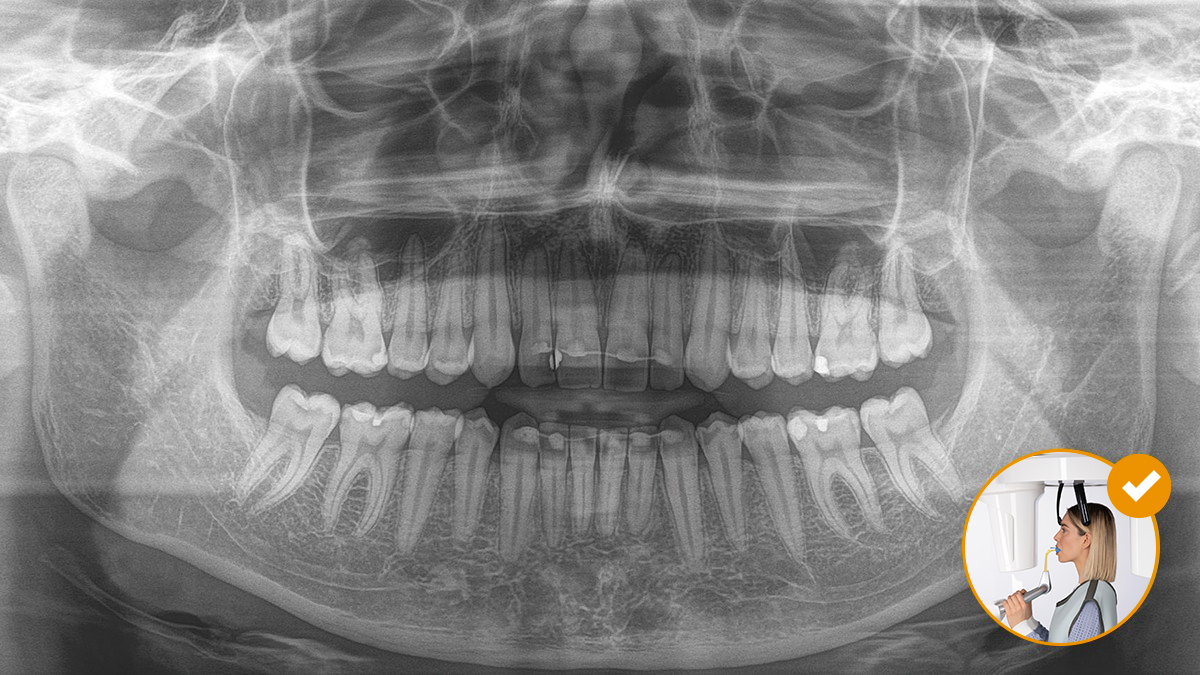

Un correcto posicionamiento del paciente contribuye a mejorar su experiencia, ya que con imágenes de alta calidad se consigue un diagnóstico más preciso.

Este concepto de 10 puntos facilita la colocación del paciente y la adquisición de imágenes radiológicas. Se fundamenta sobre todo en dos aspectos: unas imágenes de alta calidad y la mayor comodidad para el paciente y el asistente.

7. La compensación automática de la columna facilita una mejor calidad de imagen panorámica en la región anterior